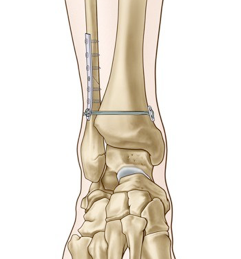

La Traumatología es una parte amplia e importante de nuestra especialidad y que abarca TODAS aquellas lesiones ocasionadas por un traumatismo, que afecta en mayor o menor grado al aparato locomotor.

Se caracteriza habitualmente por una situación de stress, ocasionado por un traumatismo, que provoca una fractura, luxación, herida, rotura tendinosa, ligamentaria, etc y que muchas veces requiere una atención urgente especializada, atención que muchas veces no está disponible en Clínicas de “Prestigio”.